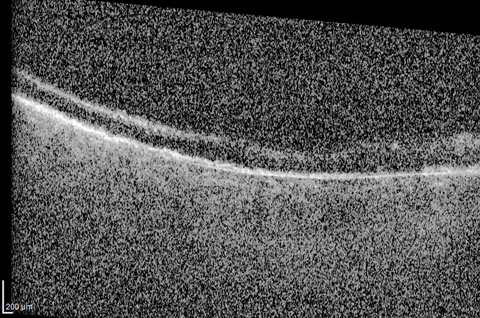

Macular telangiectasia type 2 complicated with choroidal neovascularization